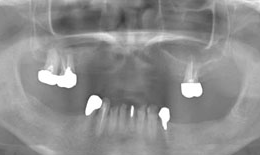

インプラント症例(2) 61歳 女性

治療方法

- 下顎

- インプラントを5本埋め込み、セラミックスクラウンを被せた

費用

| インプラント |

フィクスチャー5本 |

285,000×5=1,425,000円(税抜) |

| 上部構造(メタルボンドクラウン)5本 |

135,000×5=675,000円(税抜) |